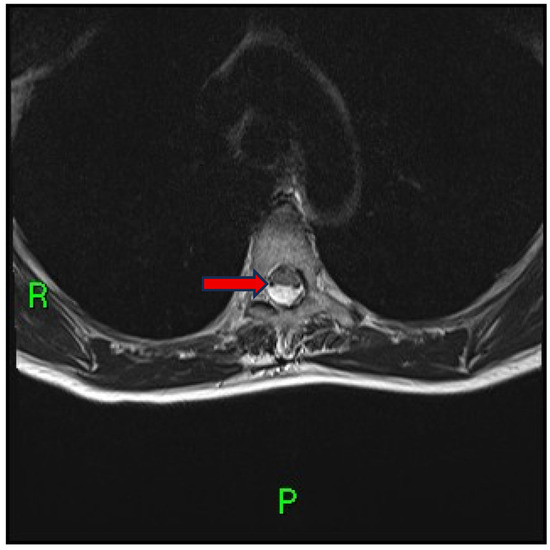

Case Report: Scalpel Sign and Dorsal Arachnoid Cyst—The Importance of an Accurate Diagnosis

2. Case Presentation

3. Discussion